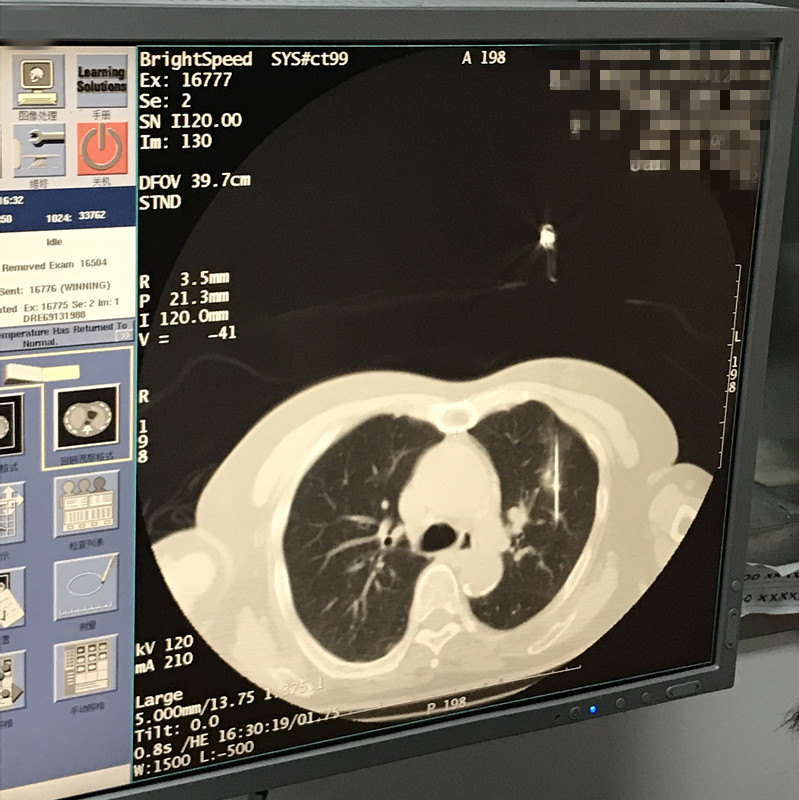

下一篇:2021年1月份肺部氩氦刀手术